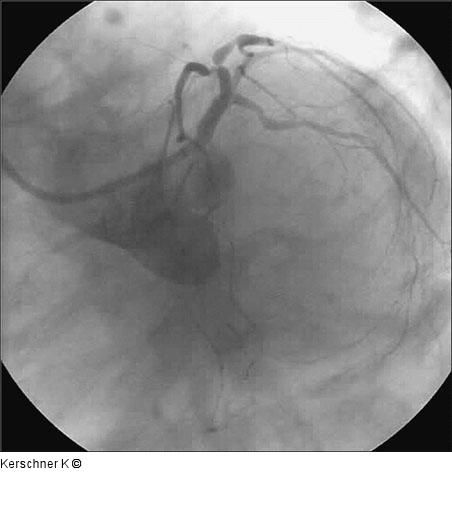

Kerschner K Patient mit Ostiumstenose-Hauptstamm und Bifurkationsstenose - R. interventricularis anterior / R. diagonalis Journal für Kardiologie - Austrian Journal of Cardiology 2005; 12 (9-10): 252 Volltext (PDF) Fallbeschreibung Übersicht

Abbildung 2: Linke Koronararterie LAO/Kaudalprojektion |